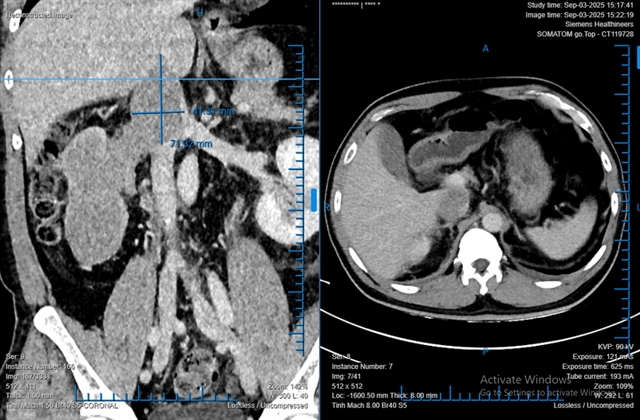

호치민시 빈단(Bình Dân)병원 의료진이 로봇만으로 신장 전체를 차지한 대형 종양과 하대정맥으로 76mm 뻗은 종양혈전을 성공적으로 제거했다.

호찌민 빈단병원에서 48세 환자의 대형 신장암과 하대정맥으로 76mm 침범한 혈전을 전신 개복 없이 완전 로봇 수술로 제거해 성공적으로 회복시켰다.